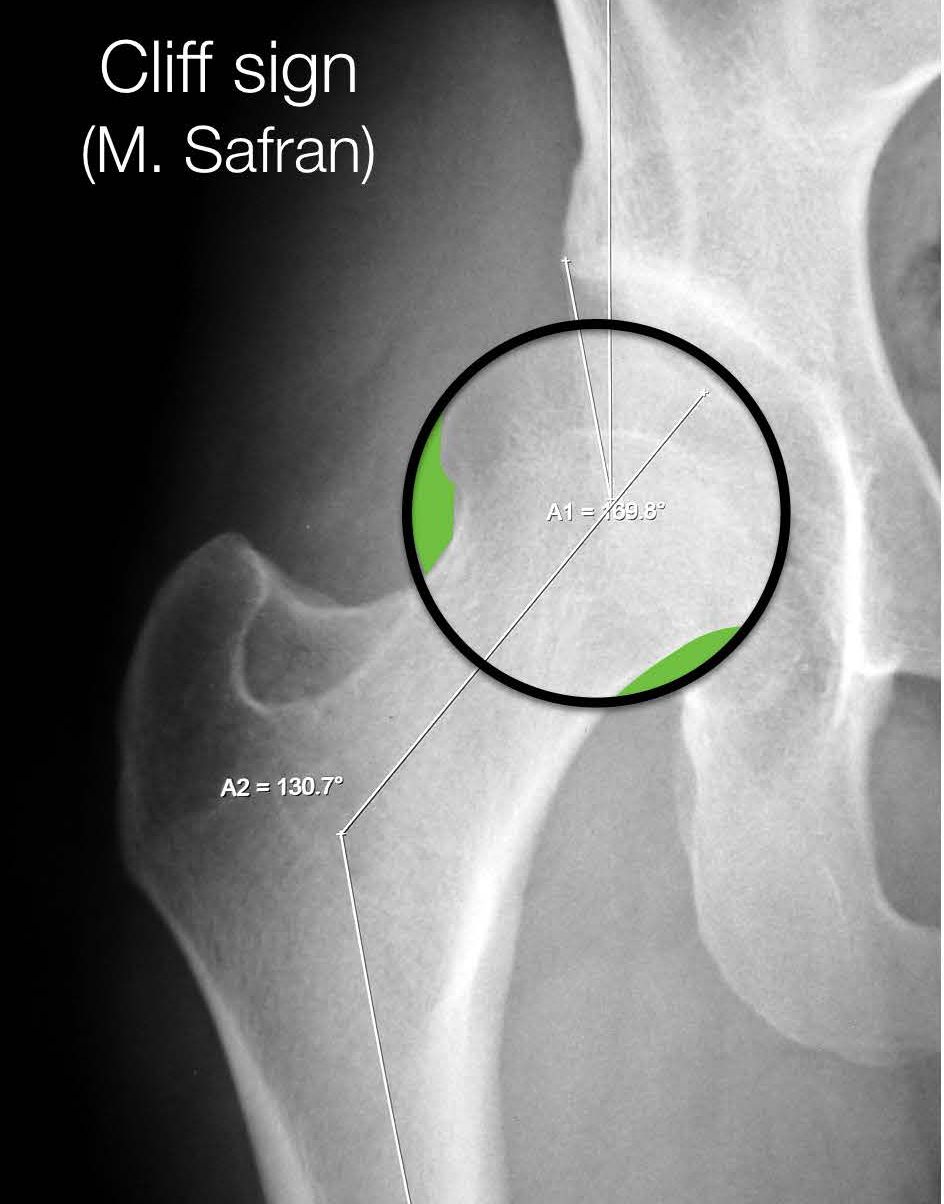

The idea came from the fact that during adolescence, the epiphyseal growth plate of the femur orients itself perpendicularly to the forces applied to it, and thus to the acetabulum. If the hip is unstable and subluxes, the growth plate is no longer parallel to the roof of the acetabulum. A recent study has validated this radiological sign in a group of 150 patients undergoing arthroscopy. The FEAR index was significantly more positive in the unstable hips compared with the stable ones (27). Finally, another excellent sign to be aware of, again described by Marc Safran, is the Cliff Sign (28). An unstable hip will nearly always have a very narrow neck and a head that is no longer a perfect circle, losing some sphericity where it ‘exits’ the acetabulum i.e. around its lateral aspect (Fig. 15). The larger the lateral empty space, the greater the sign.